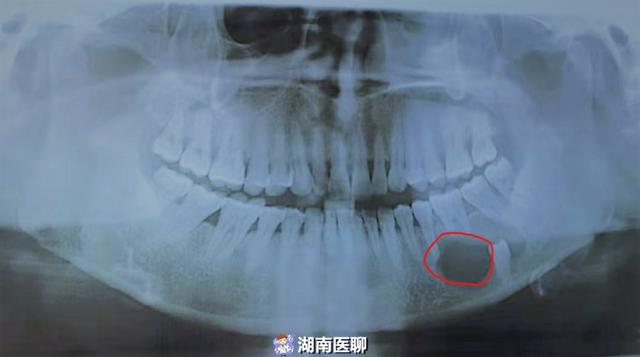

补牙之后想要拔智齿,拍完ct后,发现红圈圈的地方疑似囊肿,建议去公立

图片尺寸788x1051